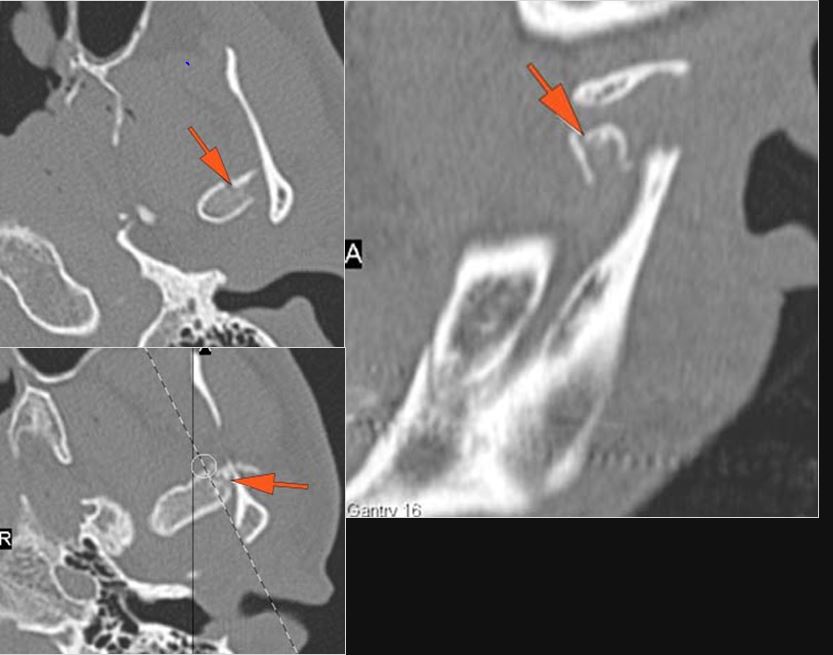

Right Temporal Bone

The ossicles, in particular the incus long process, the incudostapedial joint and stapes are fractured or dislocated.

The facial canal including the labyrinthine, tympanic and descending portions and nerve are fractured.

Left Temporal Bone